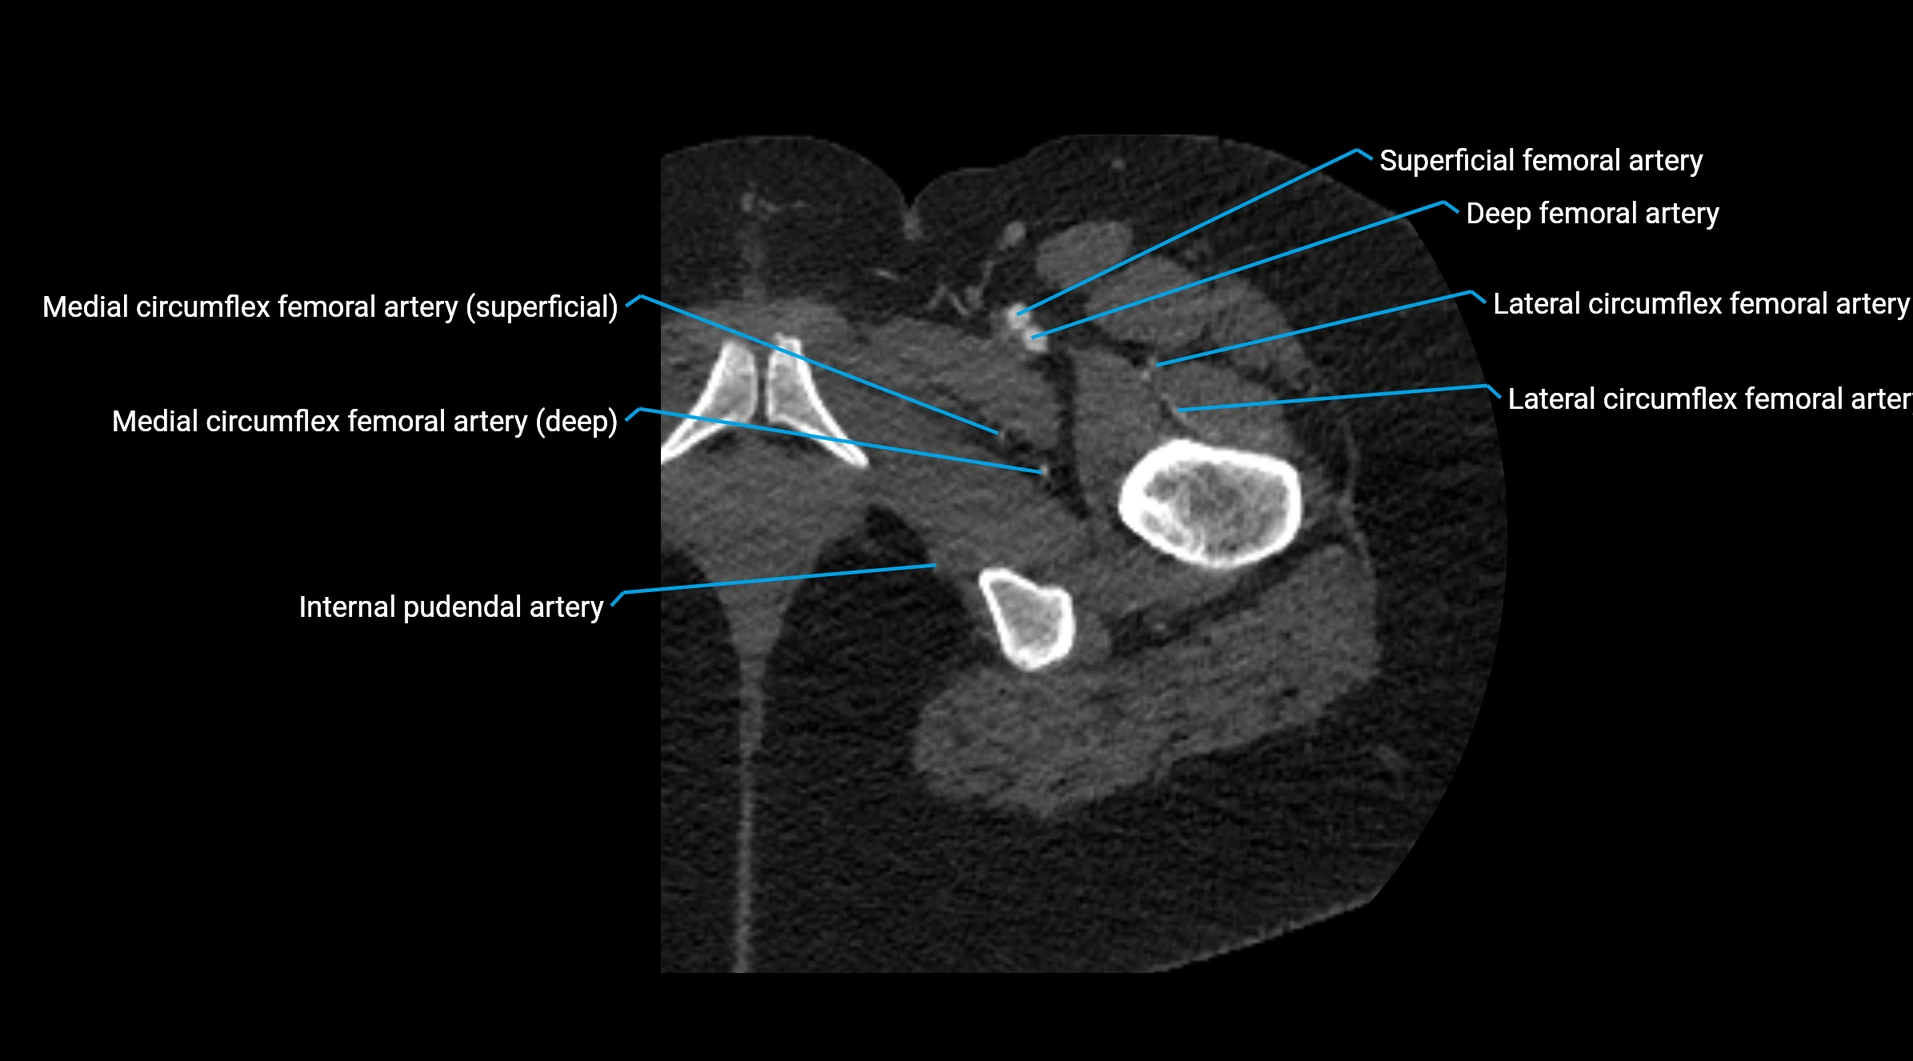

Contrast-enhanced CT (CTA):

• Gold standard for abdominal aortic imaging

• Provides excellent detail of lumen, wall, aneurysm, thrombus, and branch vessels

• Multiplanar and 3D reconstructions help in aneurysm measurement, stent graft planning, and dissection evaluation